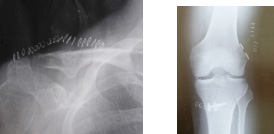

一般撮影の撮影画像

骨の画像

胸の画像